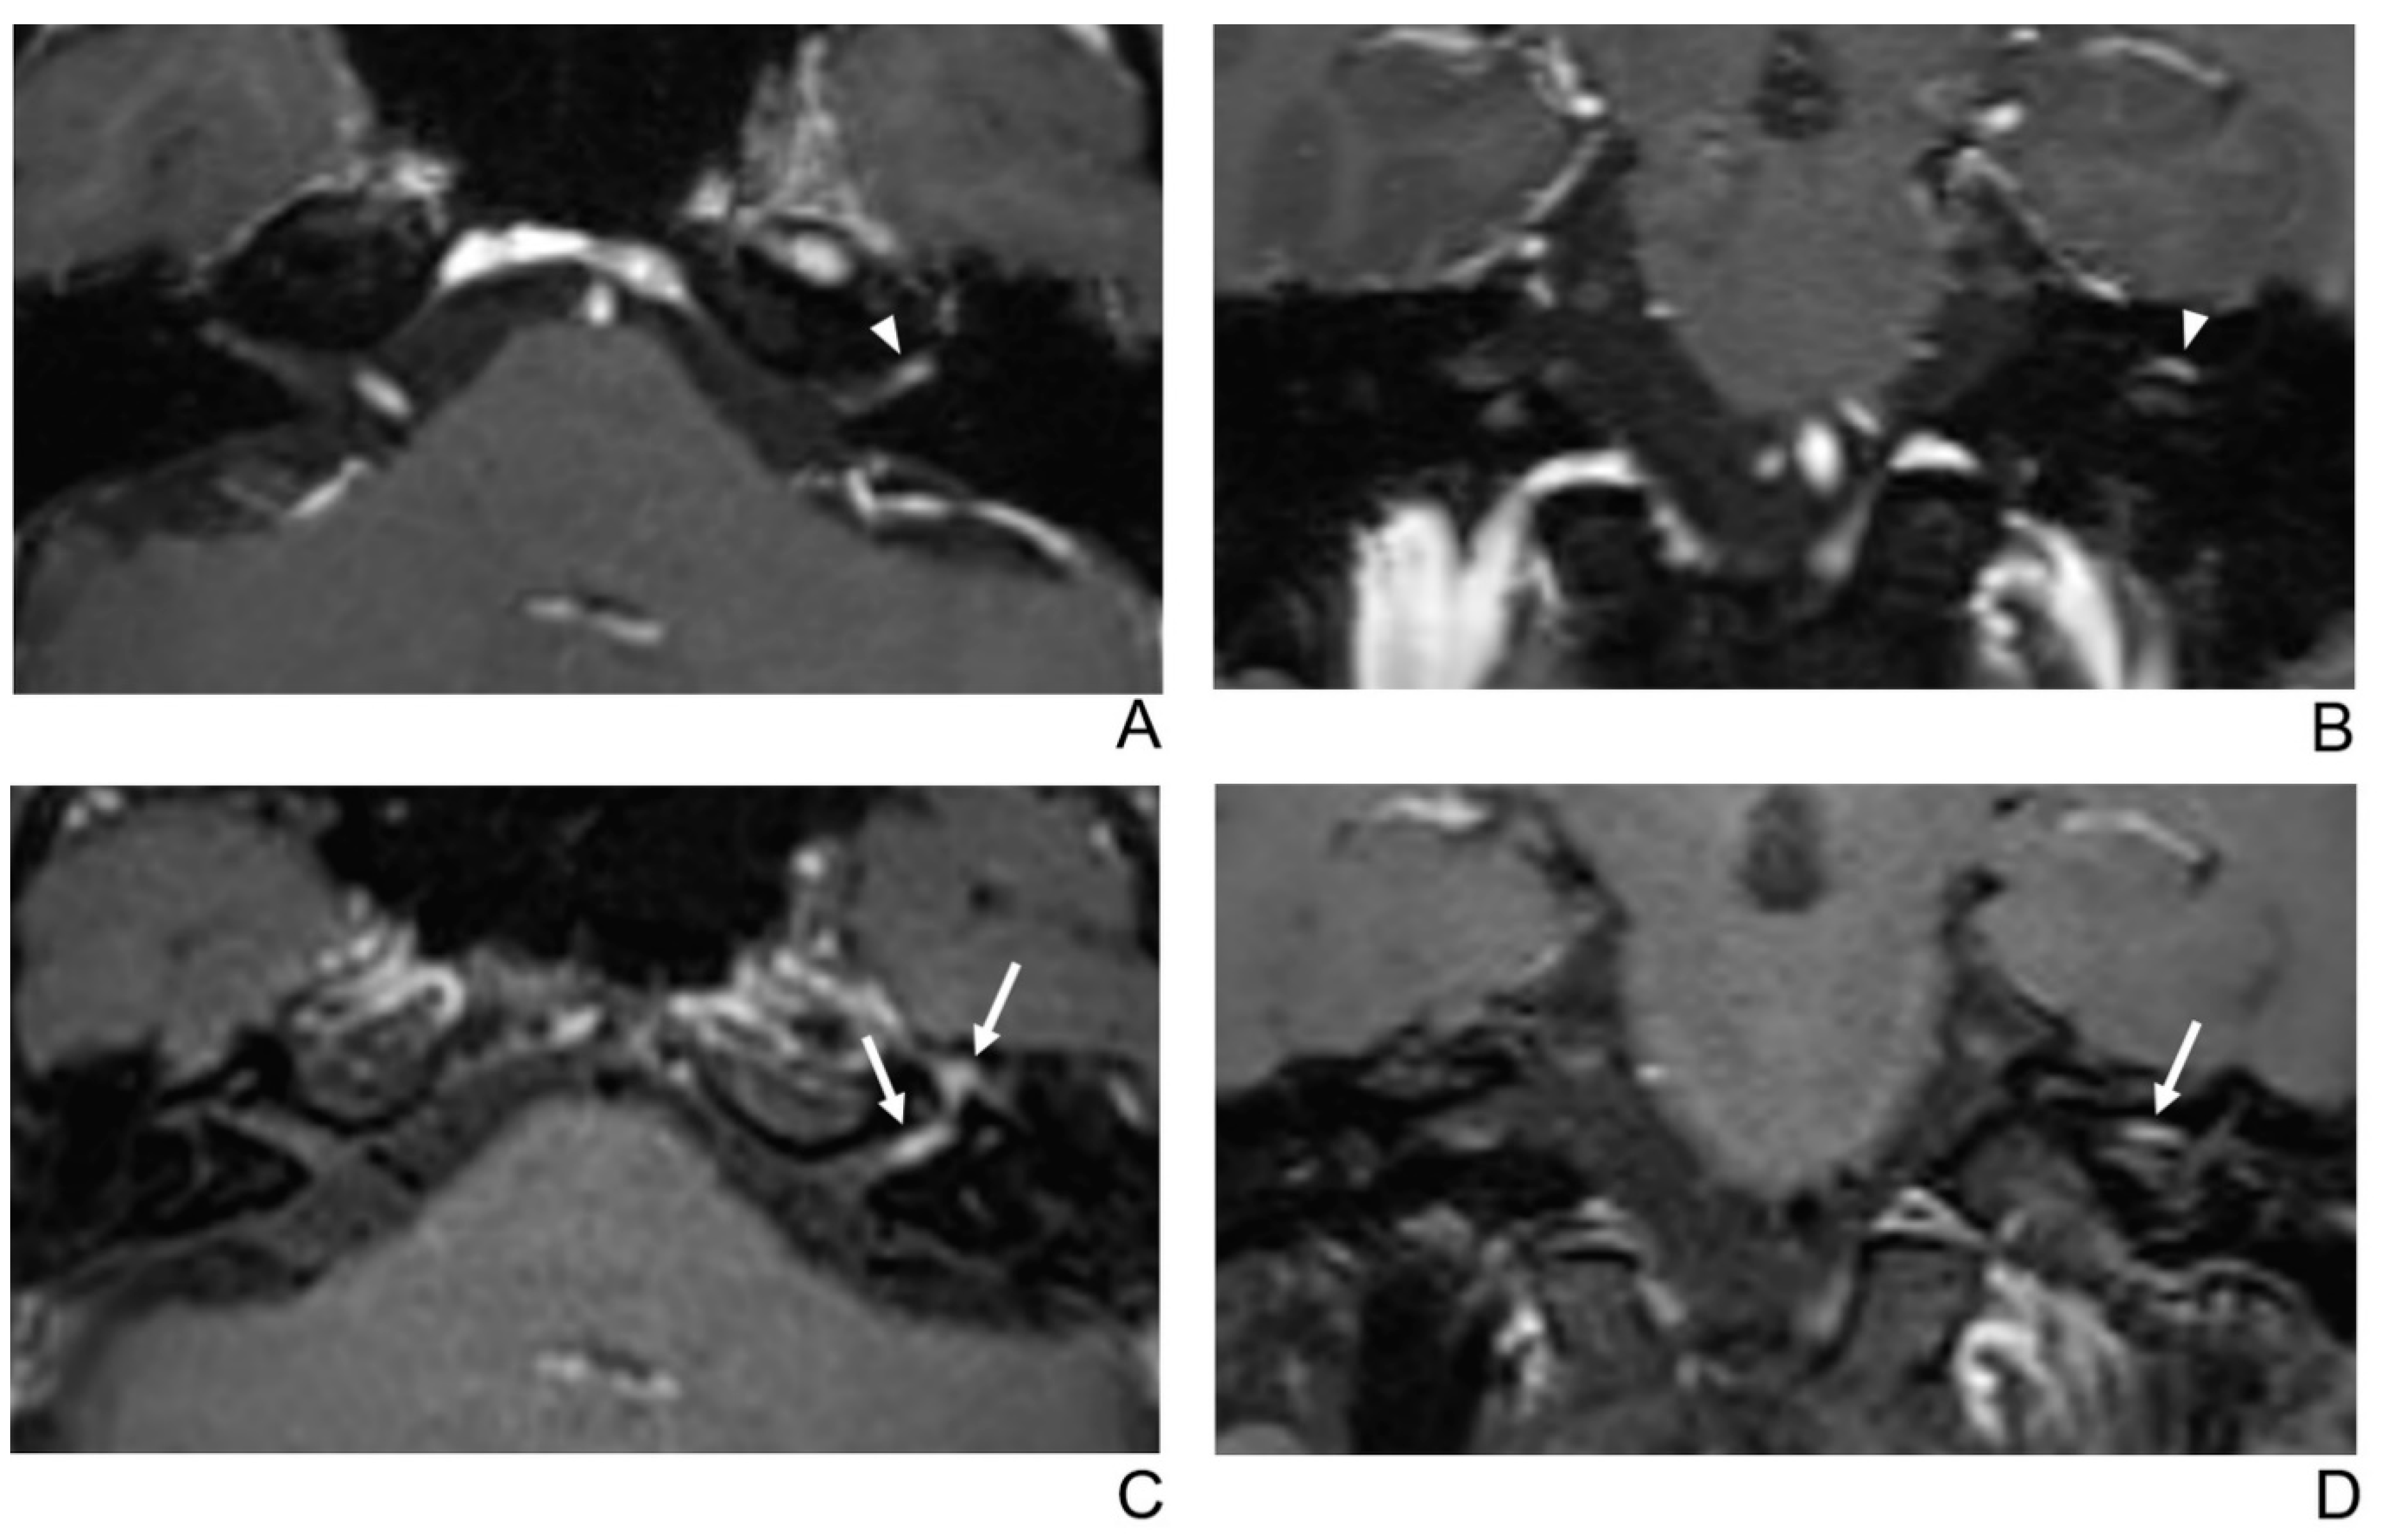

Figure 2.

A 39-year-old male patient with left facial neuritis. (A–D) Paired axial and coronal CE-GRE (A,B) and T1 BB-FSE (C,D) images of the same patient. The left distal canalicular segment of the facial nerve showed asymmetric, intense enhancement in the axial (A) and coronal (B) CE-GRE images (arrowheads). In contrast, the labyrinthine segment showed no definite enhancement, and the anterior genu segment showed moderate degree enhancement and was interpreted by reviewers 1 and 2 as left facial neuritis (2, diagnostic confidence; 3, 0, and 2, visual grades for contrast enhancement (CE) in the canalicular, labyrinthine, and anterior genu segments, respectively). The left facial nerve shows asymmetric intense enhancement in the canalicular, labyrinthine, and anterior genu segments in the axial (C) and coronal (D) T1 BB-FSE images (arrows); it was evaluated by reviewers 1 and 2 as left facial neuritis (2, diagnostic confidence; 3, 2, and 3, visual grades for CE in the canalicular, labyrinthine, and anterior genu segments, respectively). Compared to the CE-GRE images shown earlier, in the T1 BB-FSE image, it can be seen that the contrast-enhanced area in each segment of the facial nerve is longer and wider.